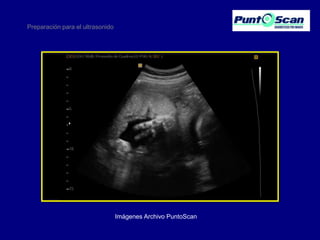

Preparación para el ultrasonido

Imágenes Archivo PuntoScan

Preparación para elultrasonido Imágenes Archivo PuntoScan